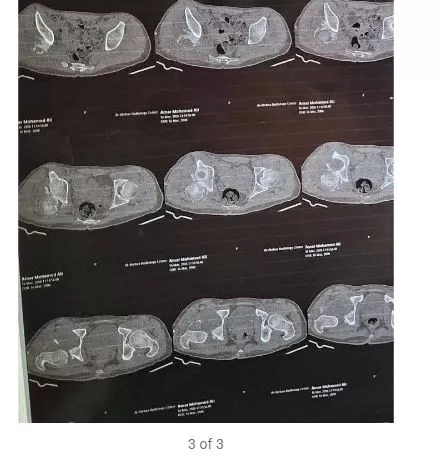

استقبل المستشفى المريض وهو يعاني من آلام حادة بمنطقة الحوض وسقوط جزئي بالقدم نتيجة حادث وقع قبل شهرين. وبعد فحوصات دقيقة، قرر الفريق الطبي التدخل الفوري لإنقاذ الحالة، حيث شملت العملية:

- إجراء رد مفتوح للخلع وإزالة التعظم بالأنسجة المحيطة.

- إعادة بناء الجدار الخلفي للحق باستخدام رقعة عظمية من عظام الحوض.

- تثبيت الكسر باستخدام الشرائح والمسامير التقنية.